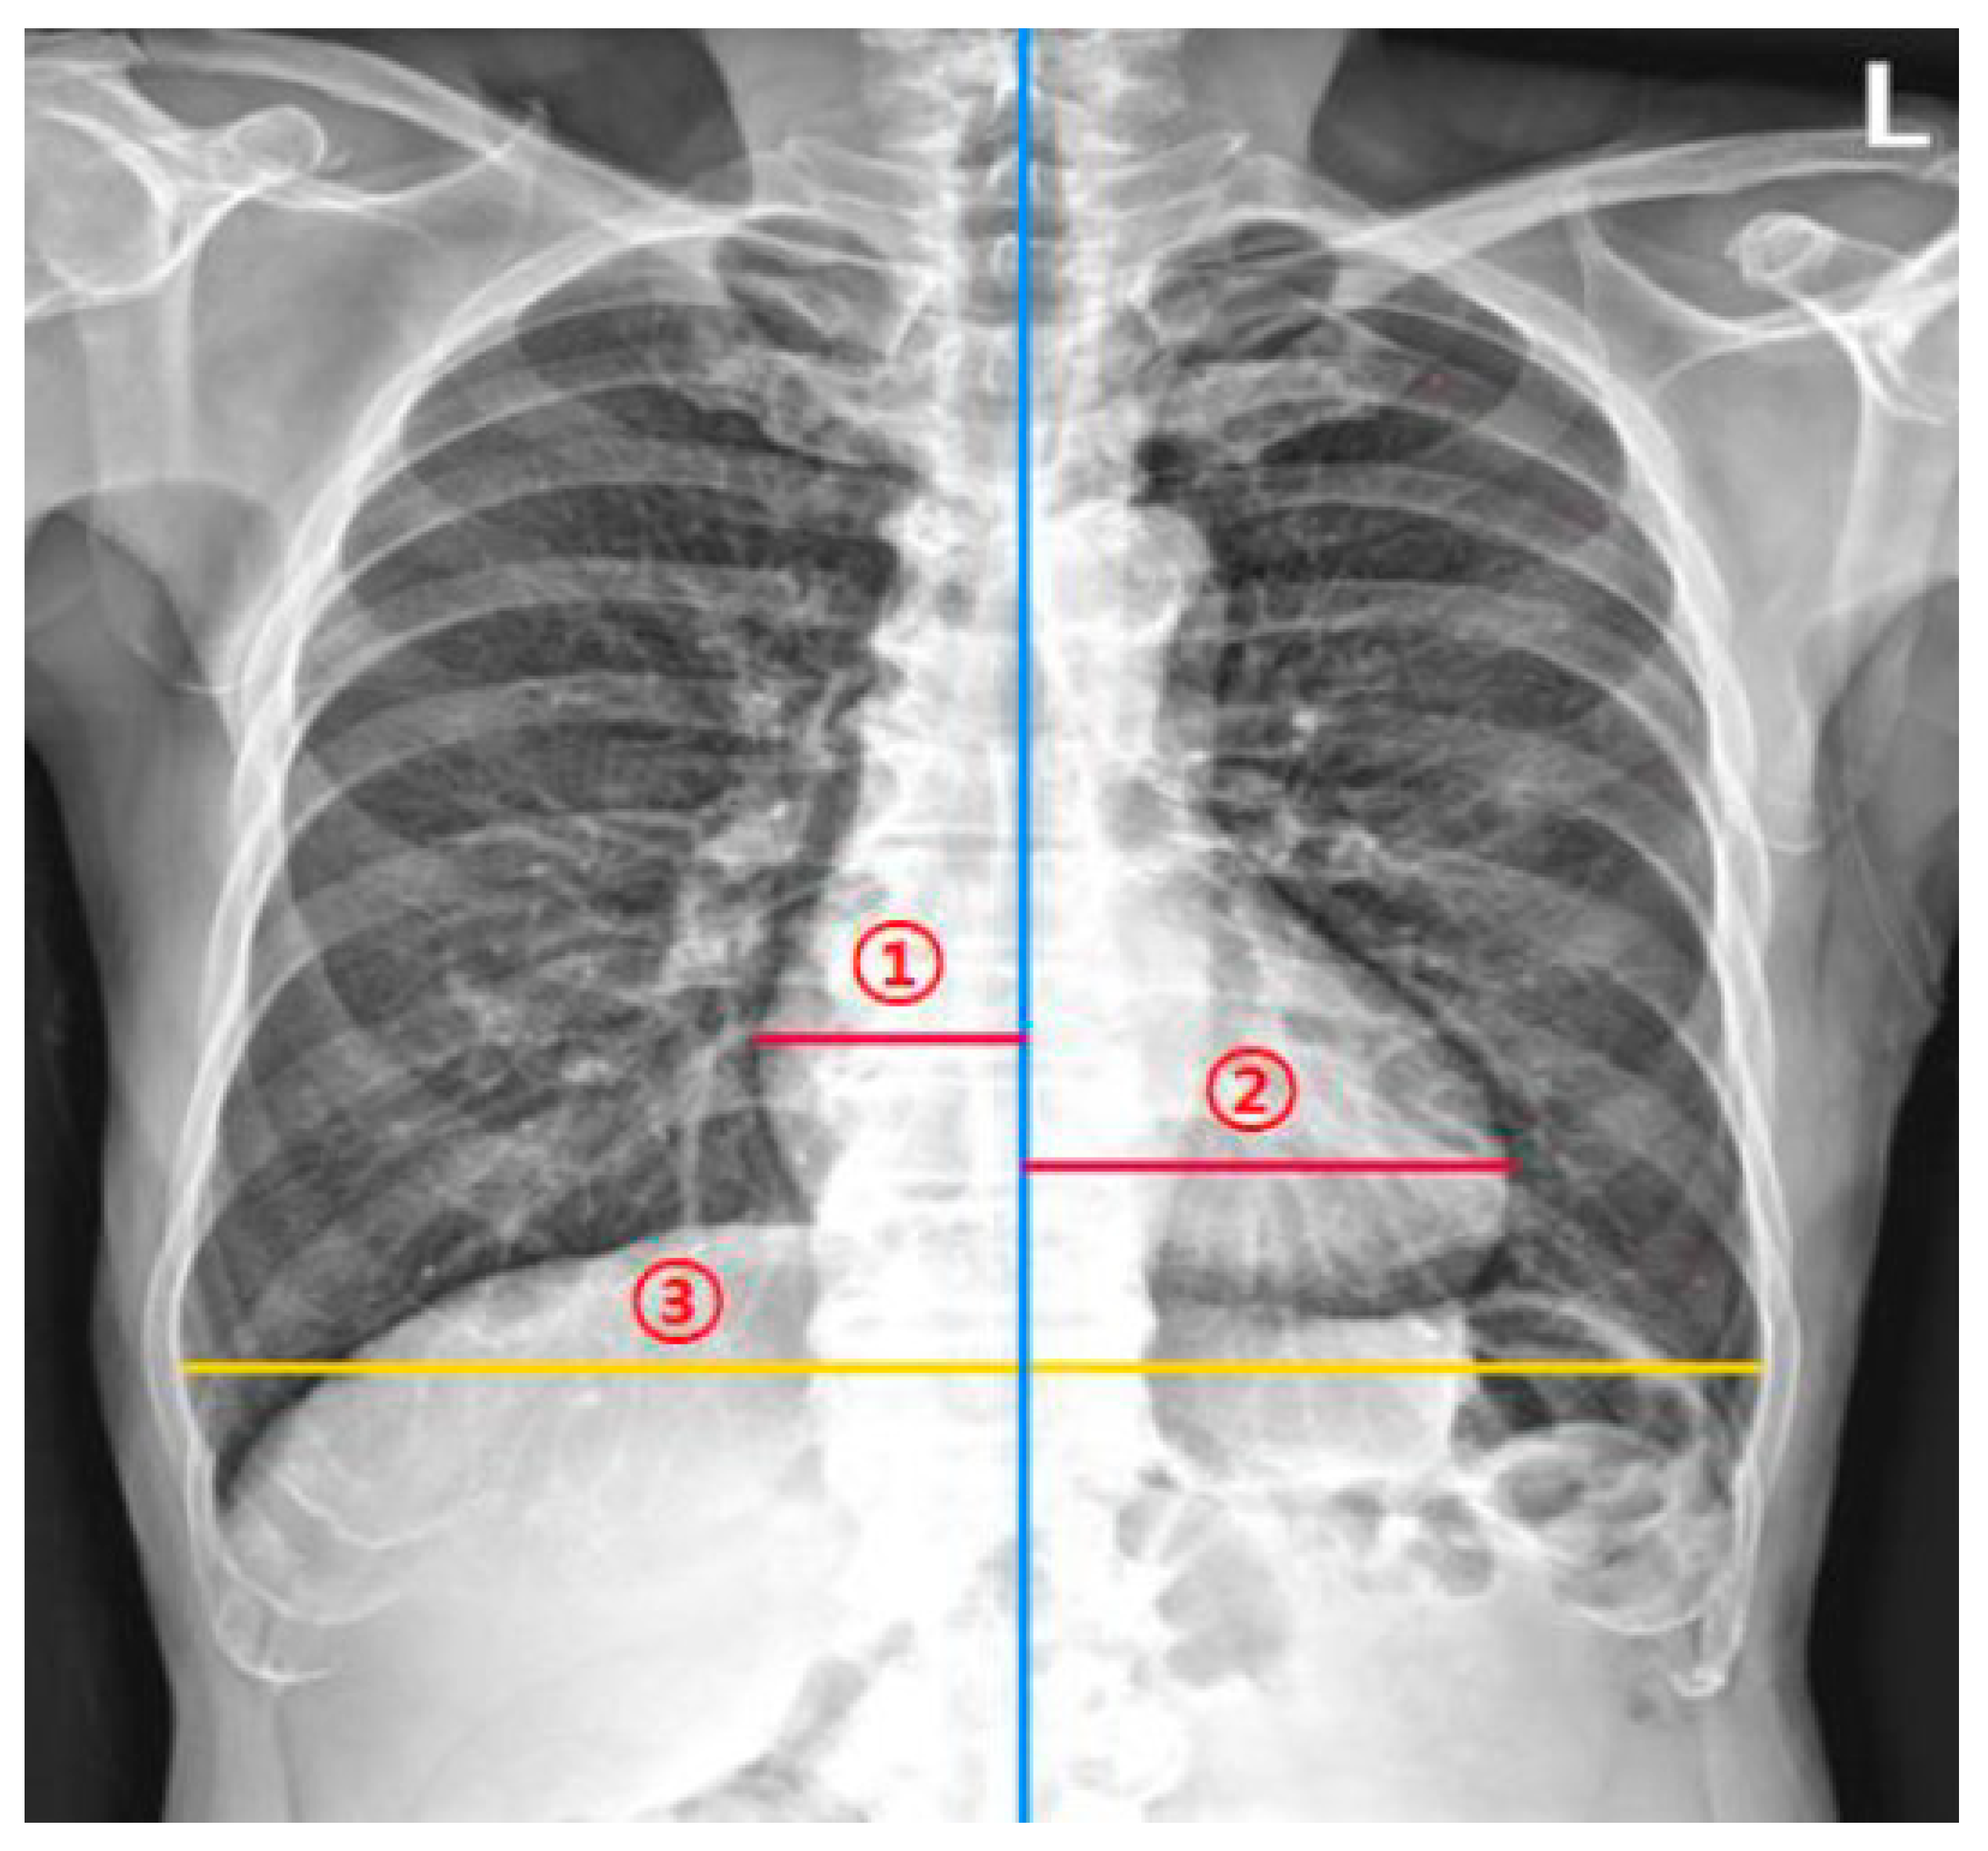

2.1. DL-Based Model Measuring the CTR on Chest Radiographs